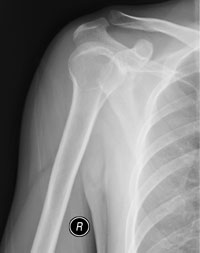

[face=黑体]请大家看看位置不一样的结果[/face]

请大家看看位置不一样的结果